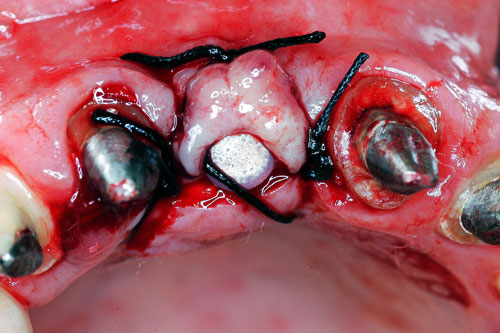

Mientras dichos movimientos ortopédicos se producen (período que supondrá otros seis meses), estudiamos los actos quirúrgicos a realizar en los cuatro implantes que pondremos. De acuerdo al estudio Desatascan realizado observamos tres situaciones diferentes: 1º-El Primer Molar Inferior Izquierdo, lo instalamos mediante Cirugía Minimamente Invasiva , con la aplicación de una Férula Quirúrgica Obtenida de los datos del scanner tratados con un programa de CMI (Cirugía Minimamente Invasiva), previa prueba en un modelo estereolitográfico, ya que la altura ósea era apenas de 9 mm. 2º- El Primer Molar Superior Derecho, se implantará mediante una ligera Elevación Atraumática (Trans alveolar) de Seno una vez logrado el espacio mesio distal necesario. 3º- El Incisivo Central Superior Derecho ausente, cuenta con un sustrato óseo prácticamente inexistente. El espesor de la tabla era de menos de 2 mm. Los caminos posibles a seguir para contar con una Rehabilitación de piezas independientes son dos: Optamos por esta segunda opción por ser menos cruenta y no necesitar de una zona dadora. Técnica esta que pondremos en práctica en dos etapas diferidas: 1º-Incisión horizontal palatinizada, incisiones peri rodetes gingivales e incisiones de descarga. Dilatación que comenzamos con dos incisiones de descarga sobre la cortical vestibular realizadas con disco. y el comienzo de la dilatación propiamente dicha mediante una hoja de bisturí, para luego seguir con un periostótomo . Recién después de alcanzada una cierta separación de la cortical vestibular de la palatina, empezamos con los dilatadores roscados. En este punto podríamos haber utilizado sin riesgos un Implante de 3,8 mm de diámetro, pero a fin de mejorar la estética del pilar emergente decidimos rellenar con material osteoconductor y osteoinductor (BiOss) y cubrir mediante membrana reabsorvible ( Bio Guide). 2º-Implantación seis meses después. Mientras se van cumpliendo los tiempos antes mencionados, y comprobamos reiteradamente la funcionalidad de la oclusión con los provisorios, tomamos impresiones definitivas y construimos primero el maxilar inferior, para definir en primer término la porción inferior de la Guía Anterior., y a nivel posterior Curvas y Microplanos. Para luego realizar los cuadrantes premolar- molar del superior: La espera de la regeneración ósea y sus tiempos pertinentes, más la espera de los tiempos de la implantación, nos obligaron a modificar las etapas del protocolo D.AT.O de manera de mantener la –D- mediante el sector superior de la GA. en provisorios, mientras fuimos resolviendo en forma definitiva los demás sectores. Ya pasados los meses necesarios para recrear un hueso adecuado en el área del Incisivo Superior Derecho, procedemos a resolver la implantación de dicha zona, observando que todo el esfuerzo dedicado al mismo había sido inútil, ya que la formación de hueso se produjo minimamente. Cuatro meses después tomamos impresiones del sector Antero Superior de la Guía Anterior, incluyendo el arrastre de un transfer . Seguimos modelando la encía con un nuevo juego de provisorios. Y se construye entonces el sector superior de la Guía Anterior. Se efectúa un control radiográfico a los 6 meses. Se ha intentado mostrar en esta Rehabilitación, que a pesar de las distintas circunstancias de cada paciente, siempre debemos tener en cuenta la necesidad de ejercer la DESOCLUSIÓN del caso como prioridad número uno, para luego perseguir la ALINEACIÓN TRIDIMENSIONAL de las arcadas y obtener así una OCLUSIÓN equilibrada. D.AT.O. ES EL PROTOCOLO QUE DEBEMOS SEGUIR EN TODA REHABILITACIÓN. BIBLIOGRAFÍA 1)William Mc Horris,B.S.,D.D.S. Oclusión. Con especial énfasis sobre :El rol funcional y parafuncional de los dientes anteriores. 2)Von Spee , Craff(Anatomista alemán, describió la curva de compensación de la articulación de molares y premolares).CURVA DE SPEE 1.89 3)Stuart,D.”Some aspects of the inervation teeth.”Procedings of Royal Society of Medicine.20:1675,19274)Muhleman,H. y Savdir,S”Tooth movility-its causes and significance”Journal of Periodontology ,36:153,Marzo ,Abril,1965. 4)Muhleman,H. Y Savdir,S”Toothmovility its causes and significance” Journal of Periodontology,36:153,marzo,abril,1965. 5-Oclusión y Diagnóstico en Rehabilitación Oral. 6-Anatomia Odontológica. 7-A contribution to the study of the movementes of the mandible. 8-Celenza F.W, Nadeskin J.F.,Oclusión.Situación actual. 9-D´Amico 10-Dawson P.E. 11-Huffman –Regenos. 12-Hobo S.-Takayama H.A. 13-Lucia V.O 14-Mc Horris. 15-Mc Horris. 16-Stuart C. 17-Vartan Veshnilian 18-Alvarez Cantoni H. AUTOR:Ratificación del Protocolo en Rehabilitación Bucal a pesar de las incidencias propias de cada caso clínico. A propósito de un caso.

Cubrimos con membrana reabsorvible.

Esperamos seis meses antes de implantar.

No obstante pudimos implantar satisfactoriamente mediante un implante de 4.2 mm. de ancho y 14 mm. de largo, con una nueva R.O.G.

Se construye inmediatamente un abuttment ceramizado para conformar la encía, y se prueban los núcleos de cerámica.